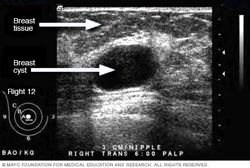

Ultrasound of breast cyst

This ultrasound shows a breast cyst.